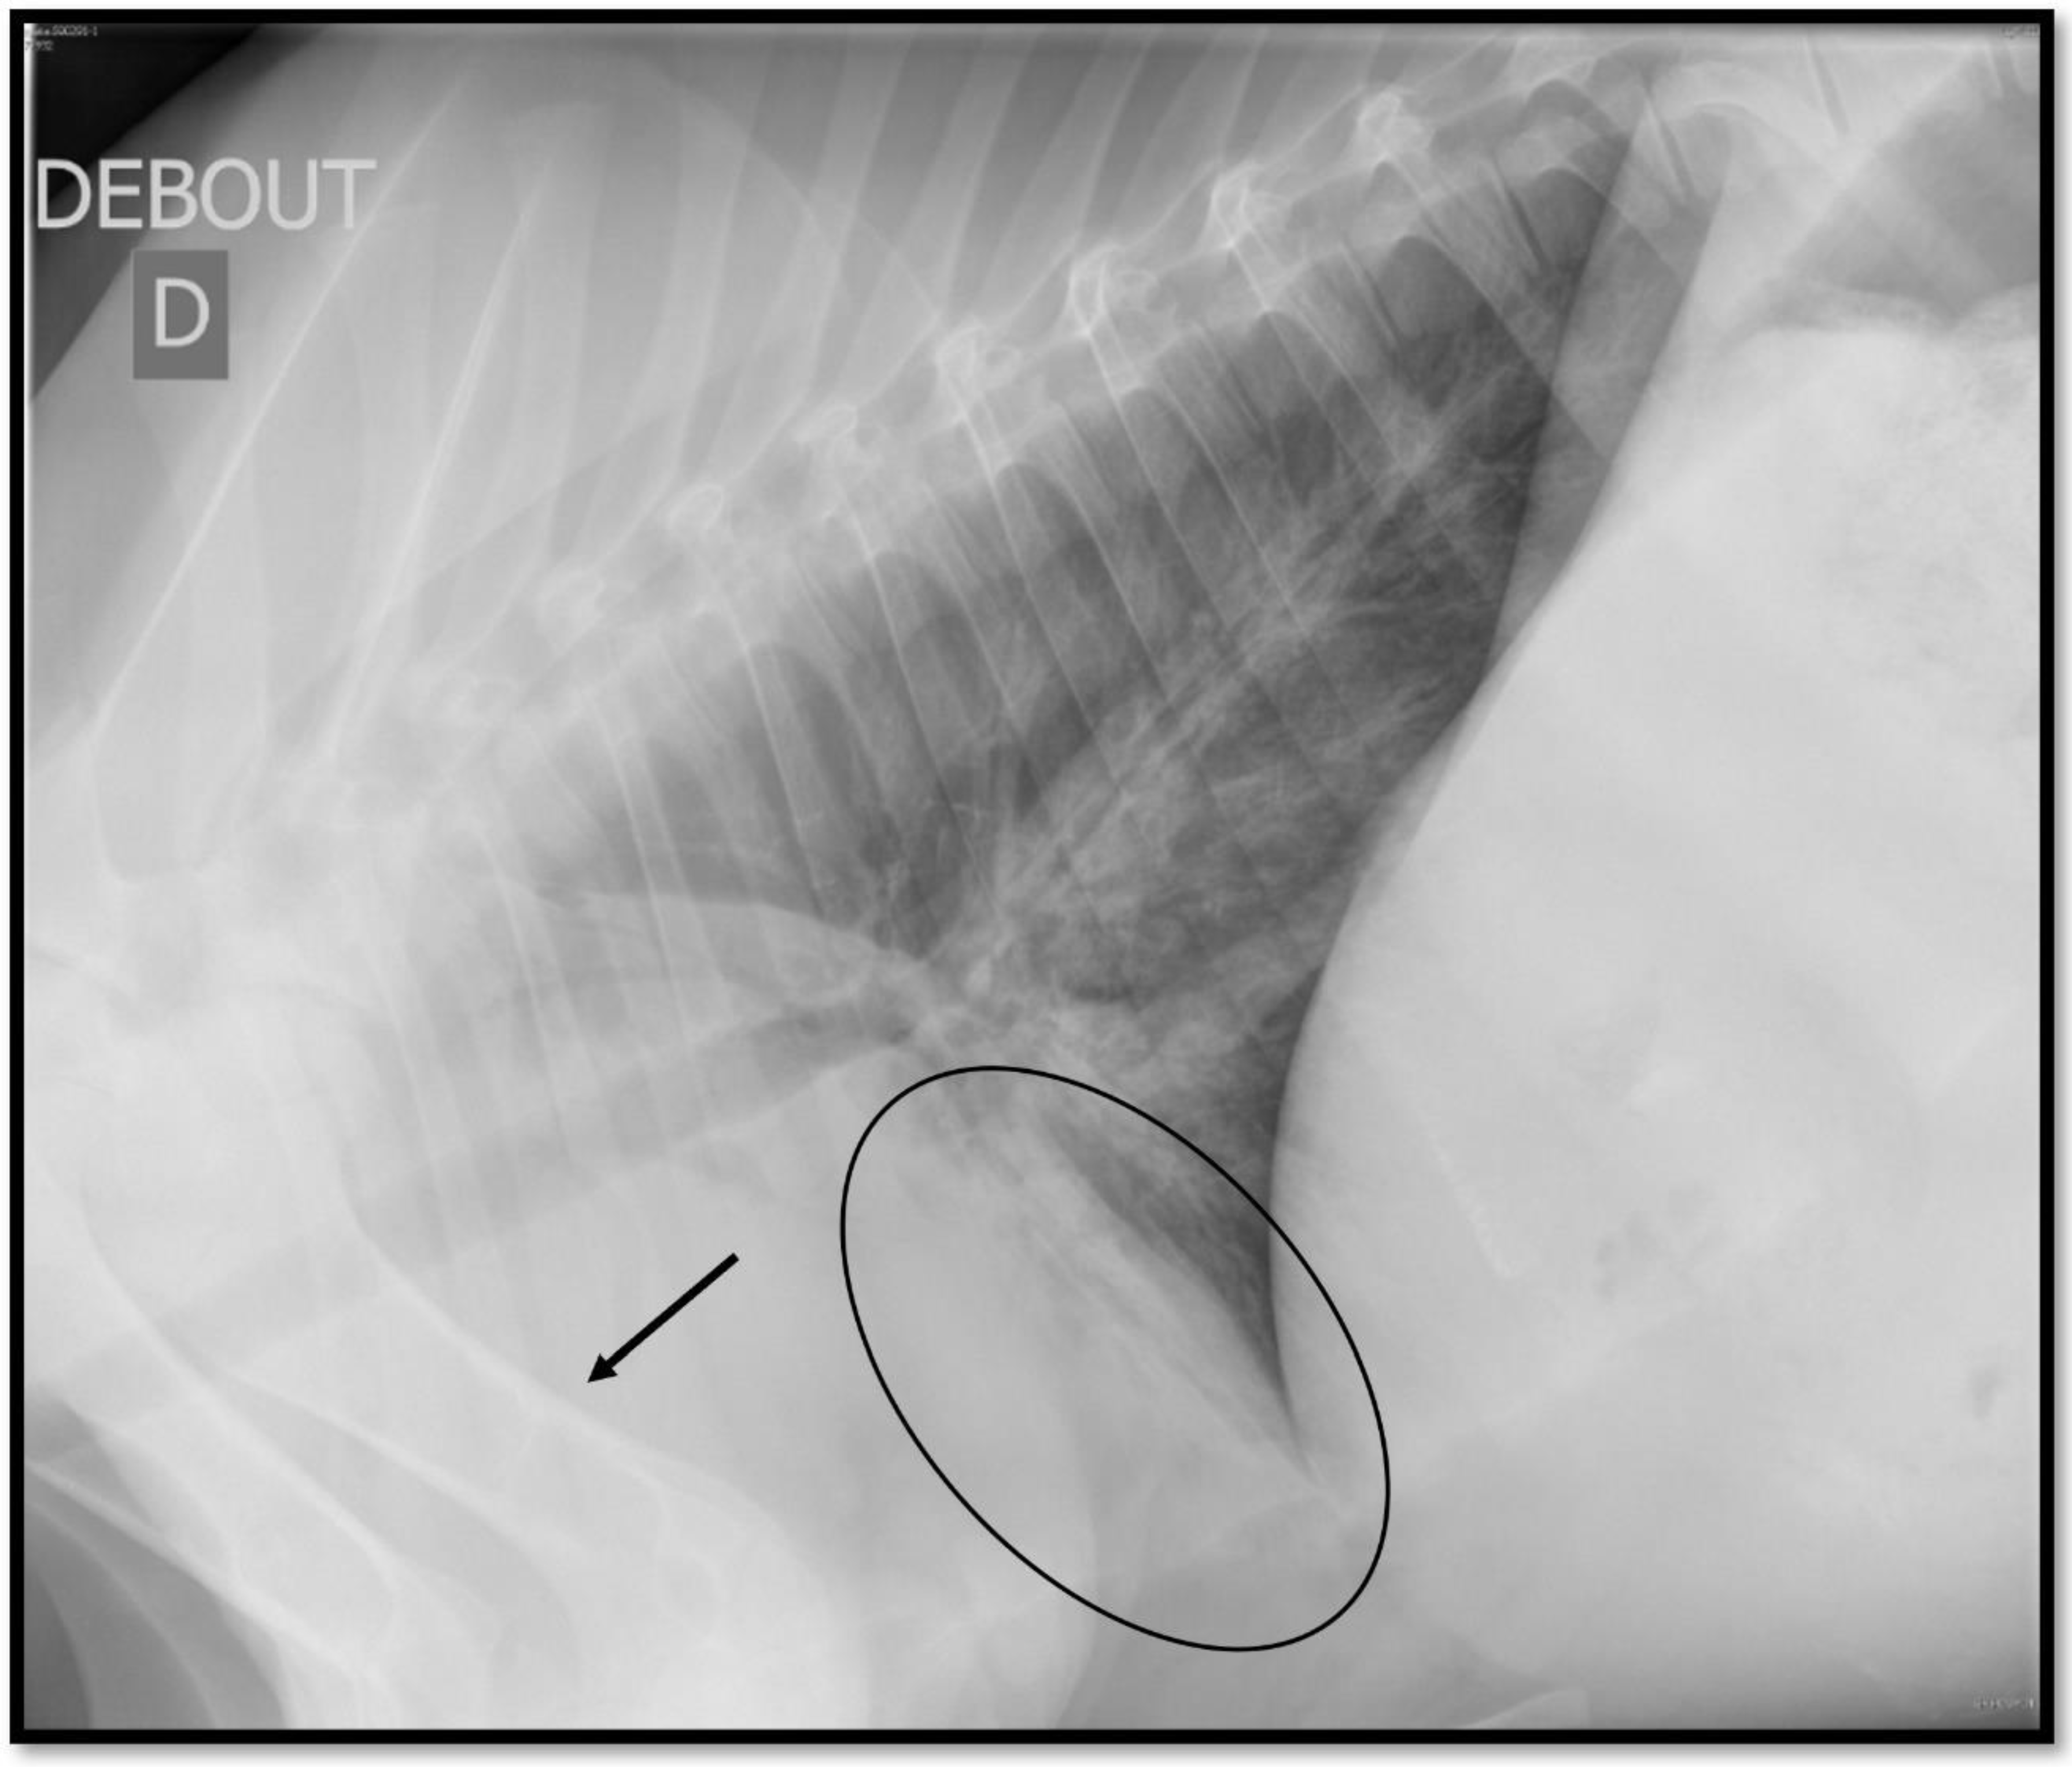

4.2. Thoracic Radiography

4.2.2. Interpretation of Thoracic Radiography

4.2.3. Performances and Agreement of Thoracic Radiography